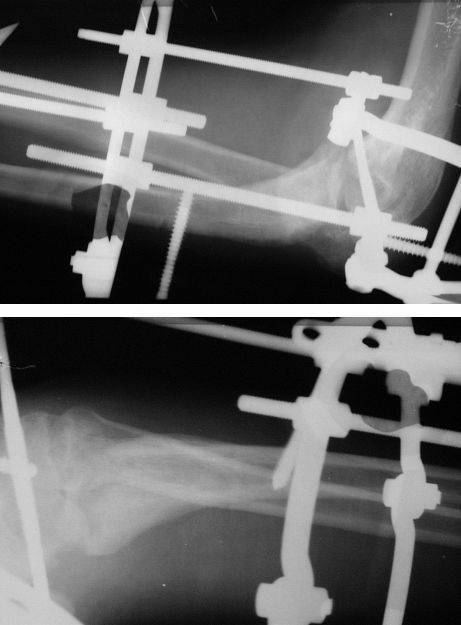

Коллеги! Сделана операция. Убрана рубцовая ткань, освежены концы до "кровяной росы", произведен релиз локтевого отростка и заднего отдела сустава - прошел до венечного отростка. После адаптации отломков выяснилось, что полное сопоставление происходит только на 1/4 периметра. Уложены аутотрансплантаты взятые из крыла подвздошной кости. Приведена схема. Через локтевой отросток проведены две спицы с упорными площадками с разбросом в 1 см, закрепленные на отдельном полукольце. Дана компрессия. Пятые сутки, рана заживает первичным натяжением. Выписываю. На 14 сутки буду пробовать движения.